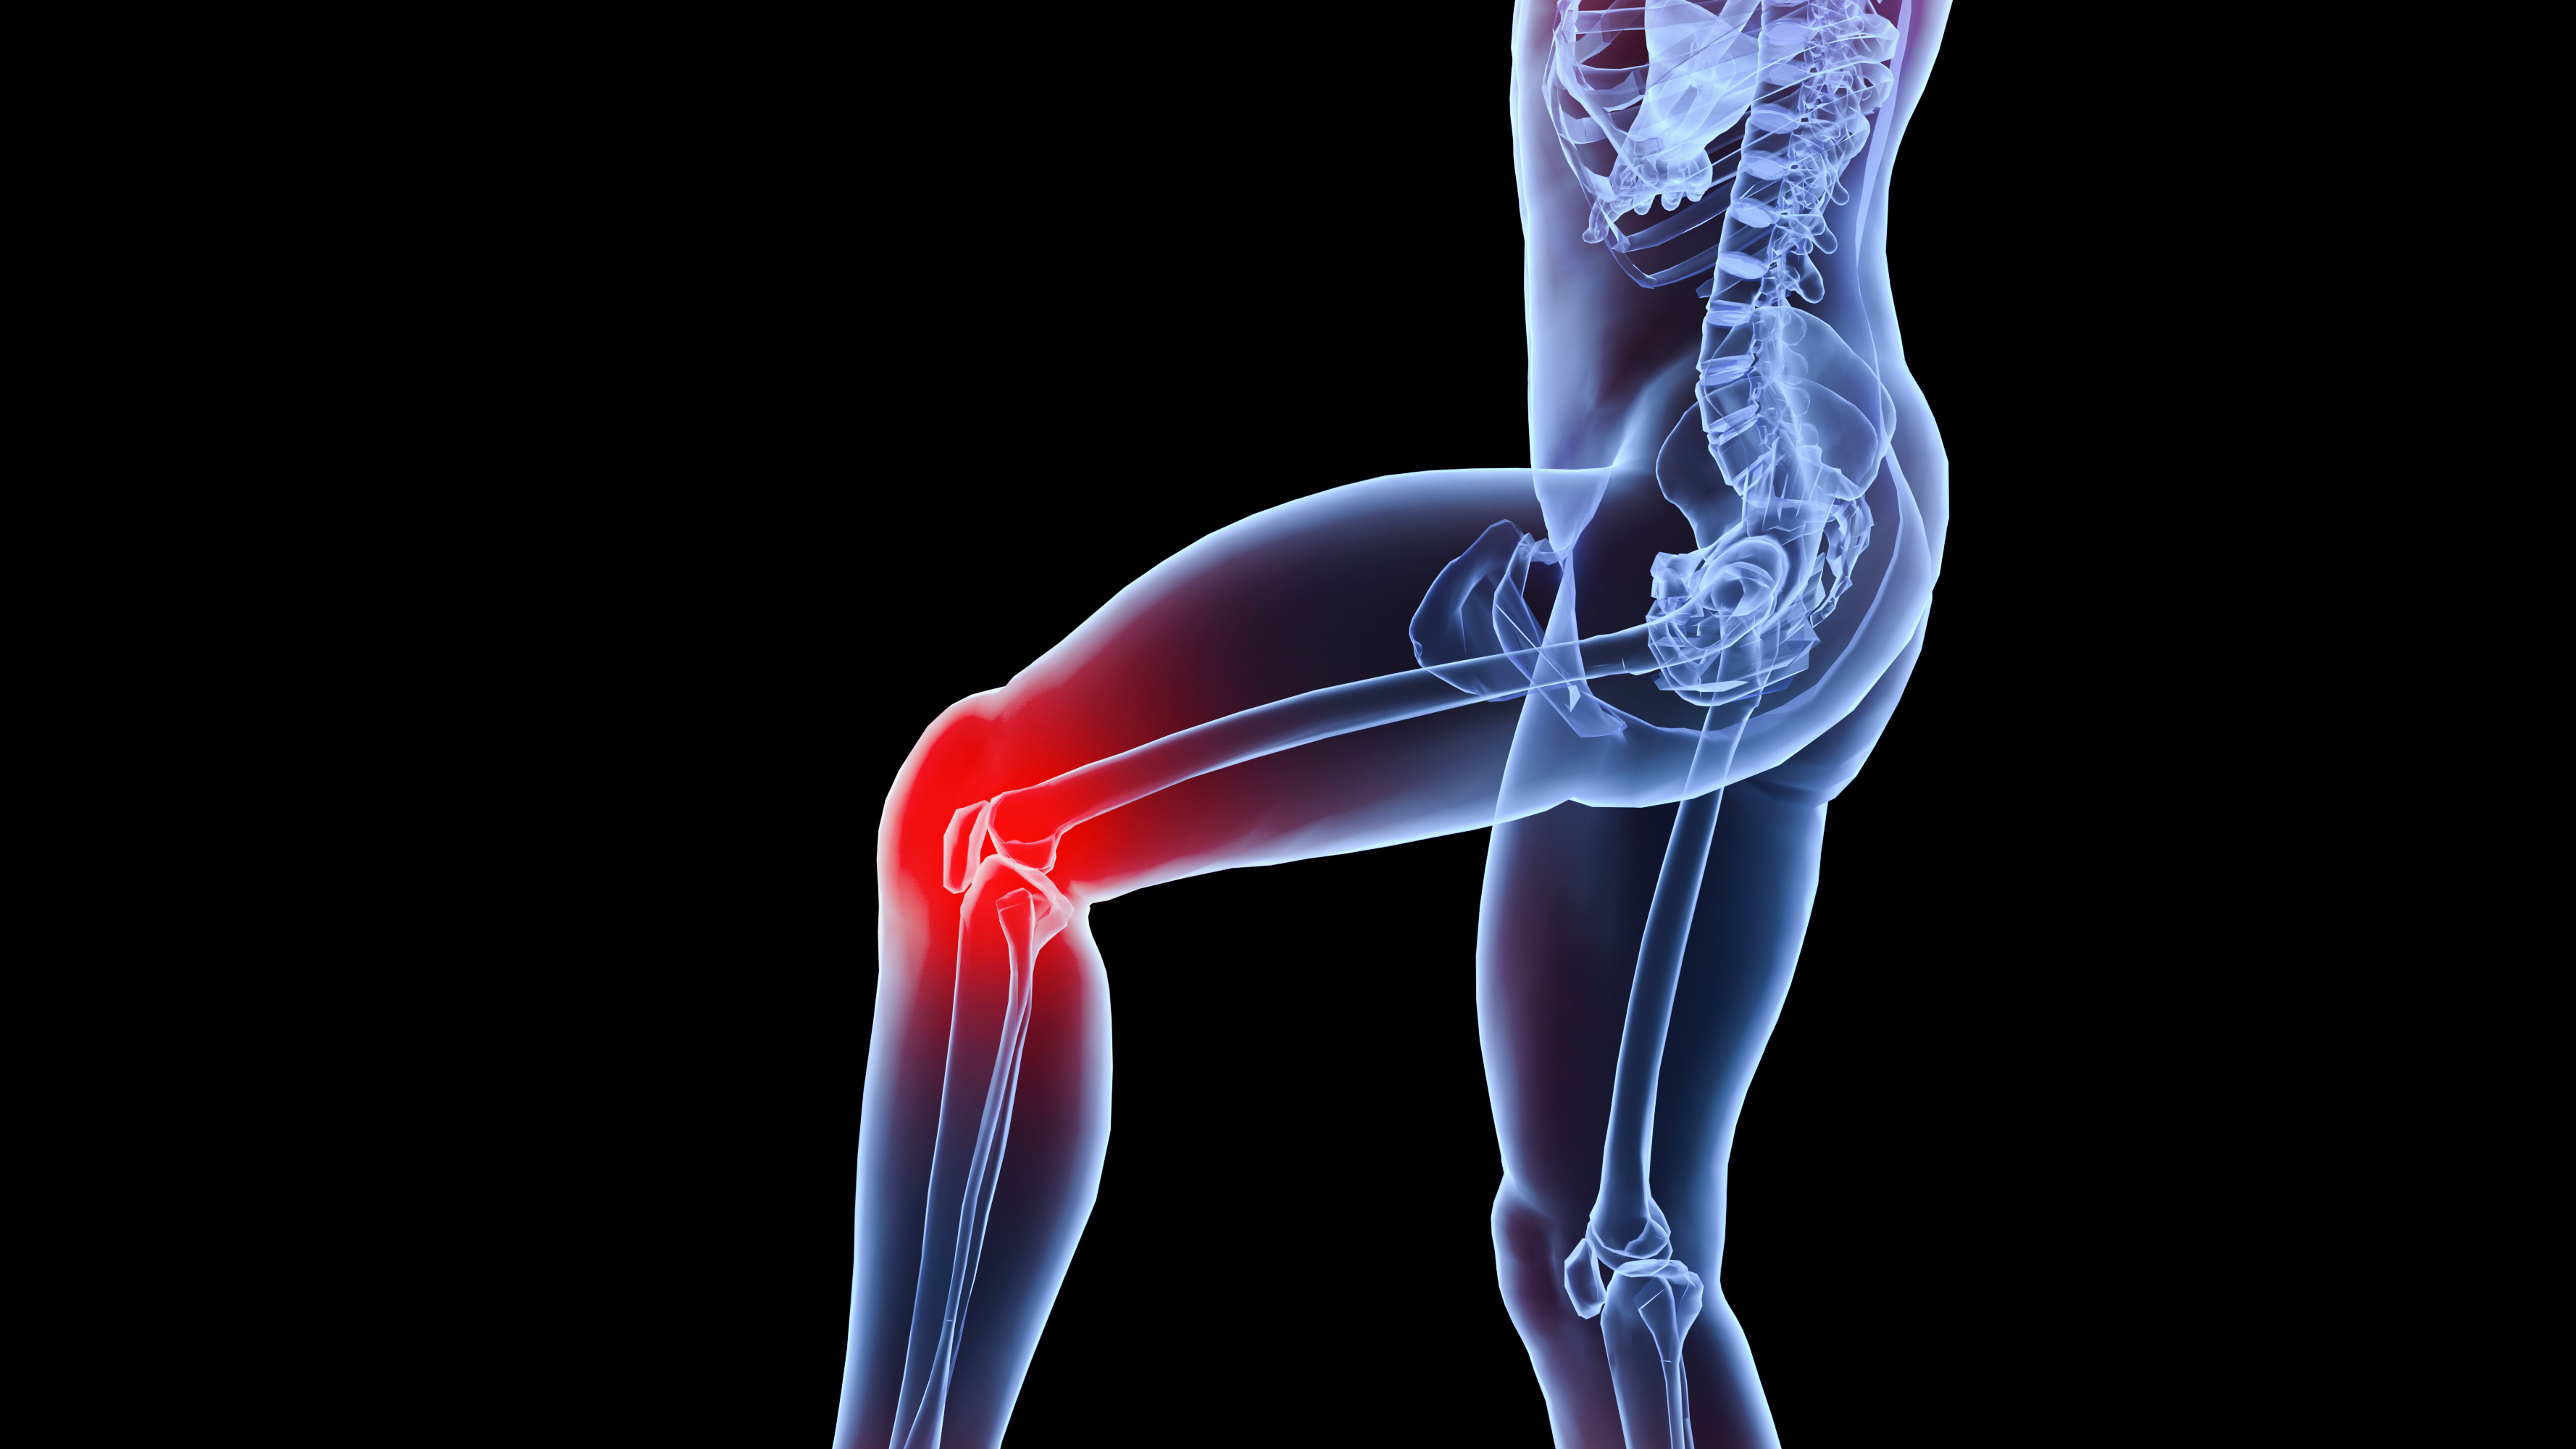

术后康复:膝关节屈曲90°活动受限的原因?